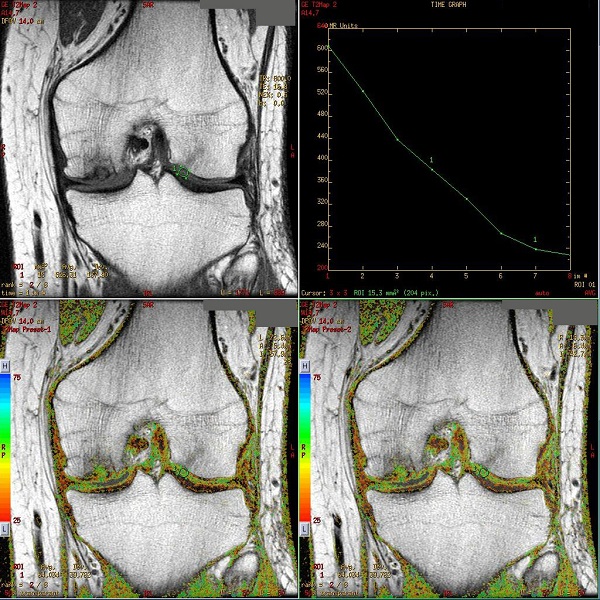

T2 Map cartigram

T2 MAP is used to noninvasively detect changes in the collagen component of the extracellular matrix of cartilage. T2 MAP acquires multiple scans at each location; each set of scans has a unique TE resulting in a set of gray scale images that represent different T2 weighting.

The acquired data can be processed in READY View to produce T2 color maps, which demonstrate more subtle changes in cartilage ultrastructure that are not visible on gray scale MR images. The T2 map and the parametric images produce visible image contrast changes in early stages of cartilage degeneration such as osteoarthritis.